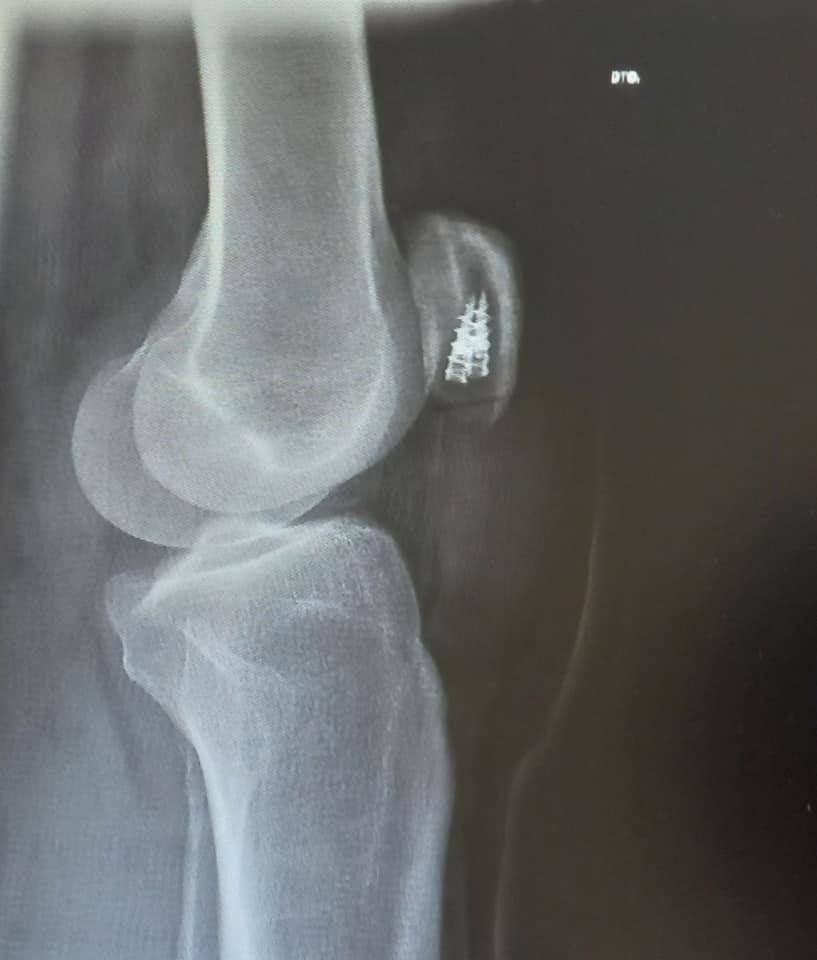

Revisão dois meses após ligeira saída de estrada. Carroçaria e demais elementos de segurança OK. Preparação e recargas de suspensão em curso. Retoma gradual de ritmo competitivo a médio longo prazo... ![]()

Entrada oficial na oficina para conseguir os alinhamentos ideais para o regresso à estrada. Simpatia e cuidados, como se querem quando o mote é voltar a curvar em condições...![]()